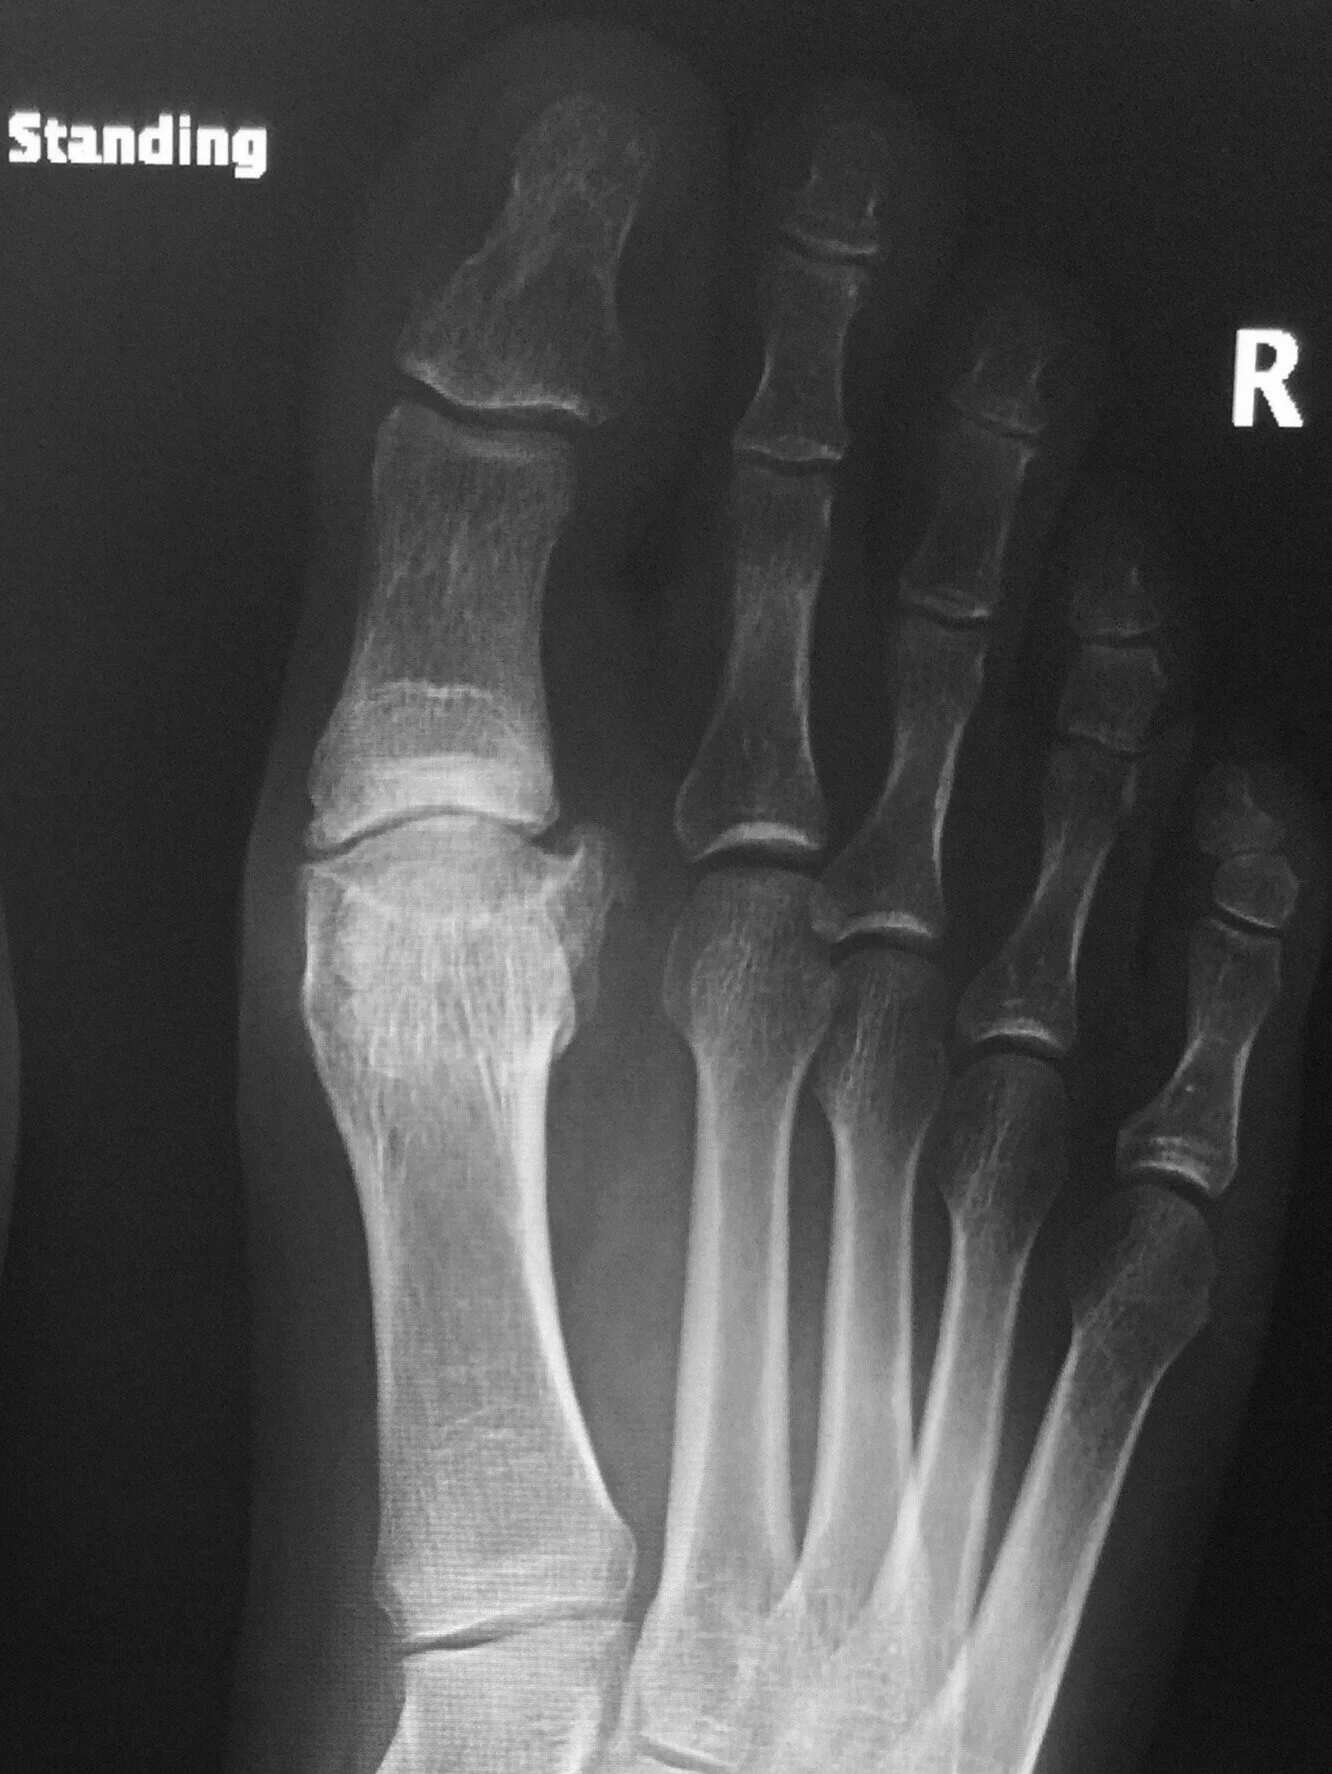

From www.alamy.com

Hallux rigidus before surgery. Xray showing foot bones before surgery to correct a case of Foot Hallux Rigidus It is the most common arthritic condition in the foot and can make walking painful and difficult. It causes pain and stiffness in the joint, and with time, it gets. However, this is not always a correct term for this. Hallux rigidus is latin for stiff big toe,. It is the most common arthritic condition of the foot, affecting 1. Foot Hallux Rigidus.